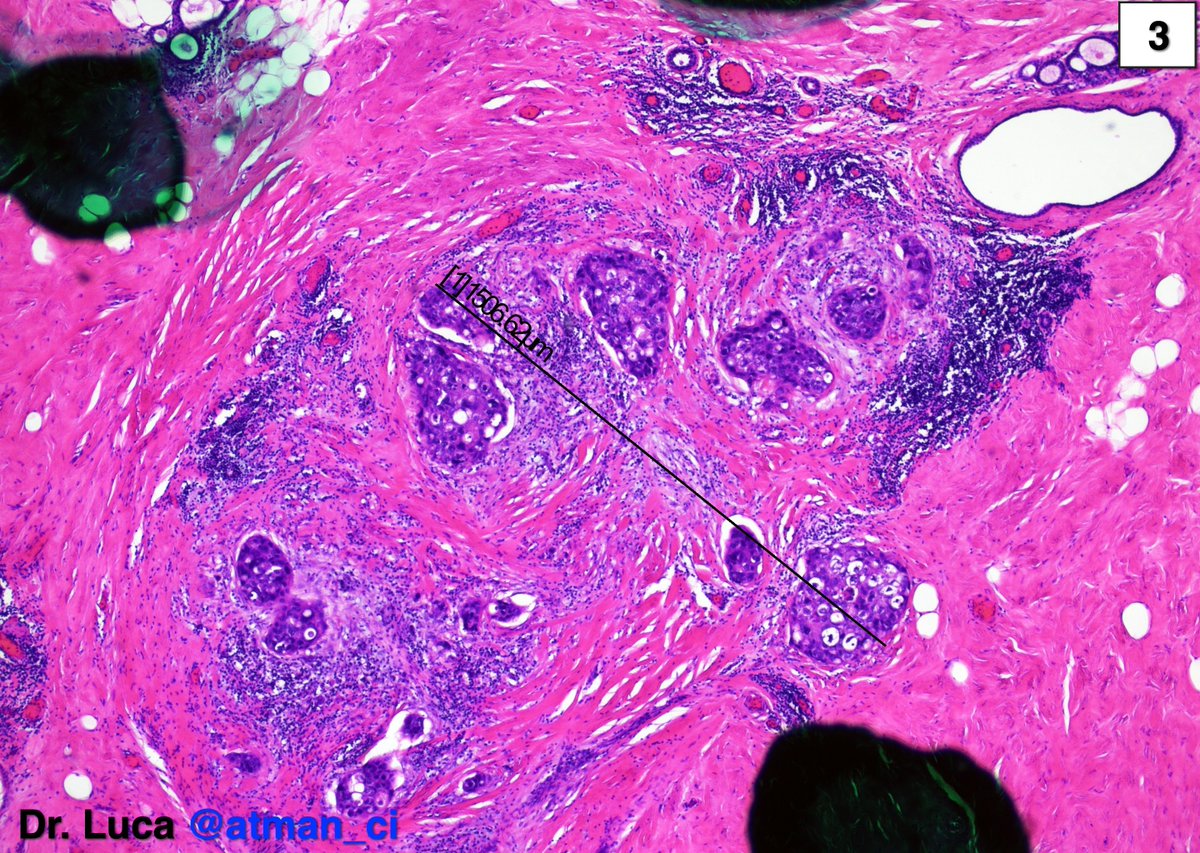

"Thanks all! MyoepIHC was + everywhere except in a µm focus (1), at the same time I resempled the specimen and I found a 2mm invasive focus (2-4). The SLN was N1(mi) @kriyer68 @LoboAnandi @QassidO @tlabiano @Jas_Bod @Ranges91 @migalf22 @bjbanji @pivonne10 #PathTwitter #BreastPath https://t.co/IIhjGU8Bcn"

(@atman_ci)